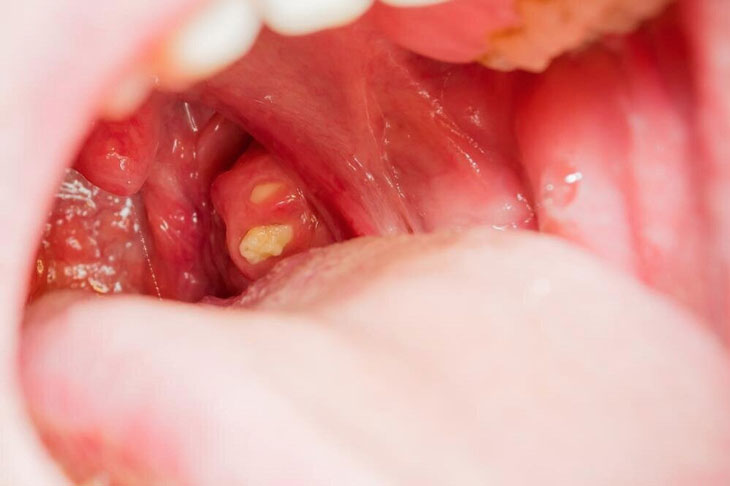

Mắc bệnh sỏi amidan

Người mắc bệnh sỏi amidan

là tình trạng bị dư thừa canxi tại các nếp gấp của amidan và sau đó những hạt sỏi này sẽ thu hút vi khuẩn cũng như thức ăn gây ra viêm họng, đau nhức và bị hôi miệng.

Trong giai đoạn bệnh mới khởi phát và chưa có nhiều vi khuẩn bám vào thành sỏi thì hiện tượng viêm họng sẽ xuất hiện nhưng không có hiện tượng ho và không sốt. Lâu dần bệnh tiến triển trở nặng sẽ kèm theo những triệu chứng khó chịu hơn và dấu hiệu ho kèm theo sốt sẽ từ đó mà xuất hiện.

Hiện tượng ứ đọng canxi tại vùng amidan sẽ khiến cơ quan này trở nên sưng, viêm nhiễm dẫn đến tình trạng nghẹn khi nuốt, không khó để phát hiện bệnh lý này vì người bệnh có thể tự quan sát thấy những đốm trắng nhỏ màu vàng hoặc trắng bám chặt vào các hốc amidan của mình.

sỏi amidan Sỏi amidan giai đoạn đầu sẽ có hiện tượng viêm họng sẽ xuất hiện nhưng không có hiện tượng ho và không sốt

Sỏi amidan không khó điều trị nhưng dẫu vậy người bệnh không được chủ quan mà bỏ qua triệu chứng của bệnh. Cần được thăm khám kịp thời để được điều trị bệnh dứt điểm. Nếu để lâu các hạt sỏi này có thể gây ra sự chèn ép và phá vỡ cấu trúc amidan lúc này sẽ rất nguy hiểm.